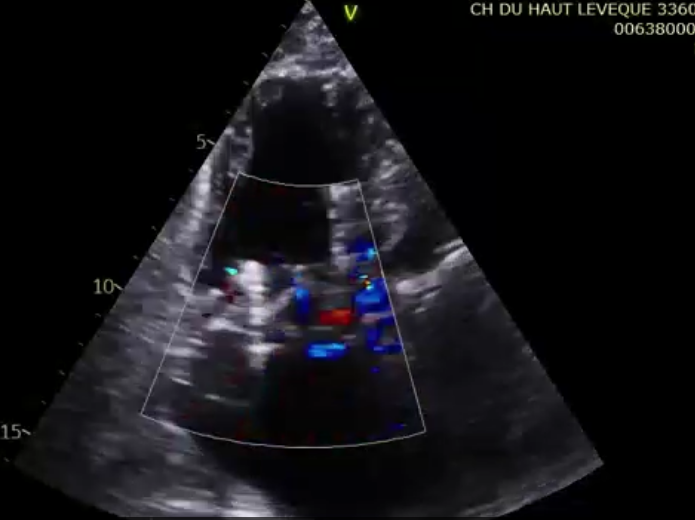

術后超聲提示微量瓣周漏